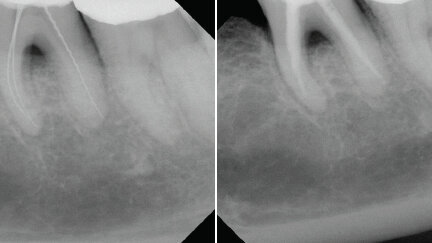

Menší kontaktní plocha, větší průžnost, vynikající preparční schopností, zvýšená taktilní kontrola, to všechno jsou vlastností, které požadujeme a které lze ještě zvýšit určitou úpravou nástrojů typu K-reamers způsobem, kdy se po celé jejich pracovní délce vytvoří pasivní odlehčená a neúčinná plocha. Výsledkem je nástroj, který má mnohém menší kontaktní plochu, je pružnější a v důsledku spojení dvou řad břitů i účinnější a v neposlední řadě umožňuje i výraznější taktilní vnímavost a kontrolu. Navíc oploštění nástroje má za následek jeho přeměnu v asymetrický nástroj, který umožní ošetřujícímu lékaři rozlišit kulatý kanálek od oválného a tím určit stupeň jeho opracování, tak aby při něm došlo k odstranění co nejvíc detritu. Mějte prosím na zřeteli, že to co se může na první pohled jevit jako nepatrná změna má za následek vytvoření nástroje, který je mnohém účinnější avšak bez sebe menšího ovlivnění jeho celkové bezpečnosti. (obr. 3)